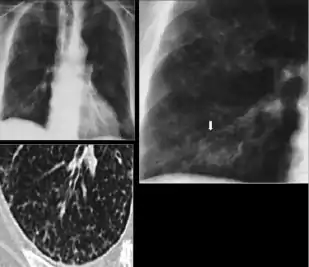

Chest X-ray of a person with advanced tuberculosis: Infection in both lungs is marked by white arrow-heads, and the formation of a cavity is marked by black arrows.

3. Nodule with poorly defined margins - Round density within the lung parenchyma, also called a tuberculoma. Nodules included in this category are those with margins that are indistinct or poorly defined (tree-in-bud sign[3]). The surrounding haziness can be either subtle or readily apparent and suggests coexisting airspace consolidation.

Chest x-ray showing nodule with margins that are indistinct or poorly defined (tree-in-bud sign) in post-primary pulmonary TB.